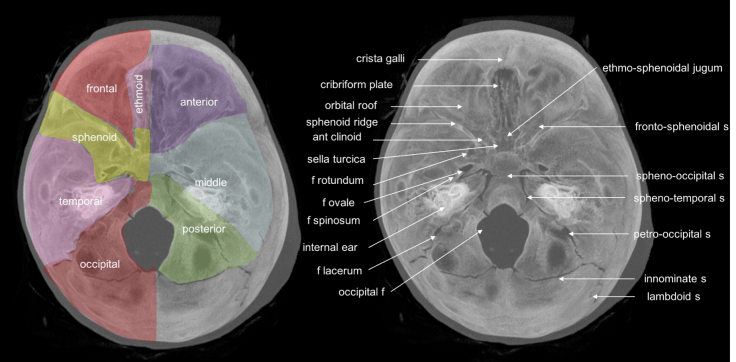

anatomie :

la base du crâne est séparée en trois étages anatomiques : antérieur, moyen, et postérieur, recoupant les os formant la base : frontal, ethmoïde, sphénoïde, temporal, et occipital ; ces os sont réunis par des sutures et parcourus de foramens laissant passage aux vaisseaux, placodes sensorielles et nerfs crâniens.

- étage antérieur : correspondant à la portion basale de l’os frontal qui constitue le toît d’orbite latéralement, descendant en dedans vers les gouttières olfactives de l’éthmoïde avec l’apophyse crista-galli au centre, il est en rapport avec les cavités aériennes du sinus frontal, qui se développe à l’adolescence, de l’ethmoïde, qui est déjà pneumatisé à la naissance, et qui continue de se développer jusqu’à l’adolescence

- étage moyen : correspondant à la grande aile du sphénoïde et à la face supérieure du rocher, il est en rapport avec le sinus sphénoïdal, qui commence à apparaître vers 2 ans ; le canal optique est particulièrement exposé par la finesse de ses parois inférieure et interne, qui font une saillie dans la cavité des sinus.

fracture du canal optique gauche avec rhinorrhée droite du fait de l’asymétrie de la cloison du sinus sphénoïdal - étage postérieur : correspondant à la face postérieure du rocher, il est en rapport avec l’oreille moyenne et les cellules mastoïdiennes, ces dernières ont la particularité de ne pas avoir de muqueuse.